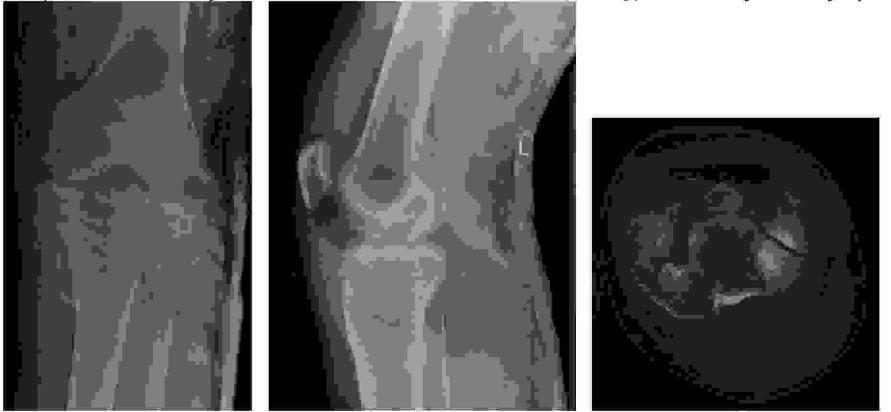

Do charakterystycznych objawów patologii widocznej na poniższych obrazach tomografii rezonansu magnetycznego należą: 1) osłabienie lub brak odruchu kolanowego, 2) ból promieniujący do kończyny dolnej wzdłuż przedniej powierzchni uda, 3) ból promieniujący do kończyny dolnej wzdłuż bocznej powierzchni uda, tylnej powierzchni podudzia, pięty, 4) osłabienie zgięcia podeszwowego stopy, 5) osłabienie lub brak odruchu ze ścięgna Achillesa.

Do charakterystycznych objawów patologii widocznej na poniższych obrazach tomografii rezonansu magnetycznego należą: 1) ból okolicy lędźwiowej, 2) parestezje, ból promieniujący do kończyn dolnych w pozycji stojącej podczas chodzenia, 3) osłabienie siły zgięcia stawu biodrowego, 4) osłabienie odruchu kolanowego, 5) zmniejszenie dolegliwości bólowych promieniujących do kończyn dolnych po przyjęciu pozycji siedzącej.